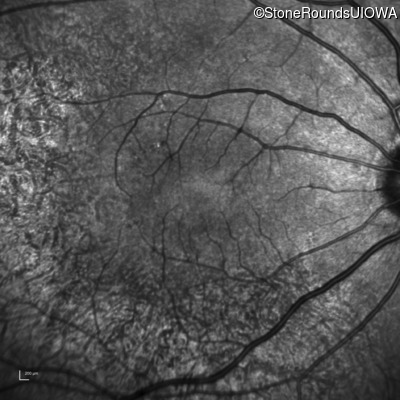

Age at visit: 63 years

OD OS